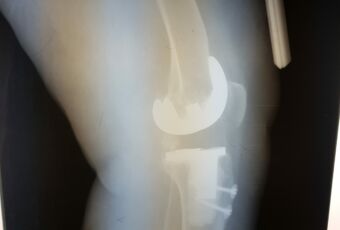

- Наименование операции: ревизионное эндопротезирование коленного сустава.

- Используемое оборудование, методика: использовался специальный установочный инструментарий для имплантации полусвязанного эндопротеза коленного сустава LCCK Zimmer, методика операции: удаление нестабильного компонента тотального эндопротеза коленного сустава, подготовка поверхностей костной ткани к имплантации ревизионного компонента, примерка компонентов эндопротеза, установка ревизионных связанных компонентов при помощи костного цемента. Операция – ревизионное эндопротезирование коленного сустава связанным эндопротезом.

- Краткая информация о пациенте, диагноз: Пациентка С., 1952 г.р. Диагноз: Асептическая нестабильность компонентов эндопротеза левого коленного сустава.

- Краткое описание хода операции (основные этапы): Иссечены рубцовые ткани по периферии сустава. Удален полиэтиленовый вкладыш и два винта с шайбами из бугристости большеберцовой кости. Затем с помощью долот и набойников удалены последовательно бедренный и большеберцовый компоненты. По направителям произведены минимальные опилы большеберцовой и бедренной костей. Затем развертками обработан канал большеберцовой кости до размера 14 мм, а бедренной кости до 17 мм. Имплантированы примерочные компоненты на интрамедуллярных ножках, отмечены дефекты, требующие заполнения металлическими блочками и стабильность сустава. После этого на 1 дозу костного цемента имплантированы бедренный компонент («Е») LCCK с ножкой 100/17 мм, большеберцовое плато 4 с ножкой оффсетной 100/14 мм, вкладыш LCCK 14 мм, 3 металлических блочка. Сустав вправлен, стабилен.

- Результат: имплантация ревизионного эндопротеза коленного сустава.